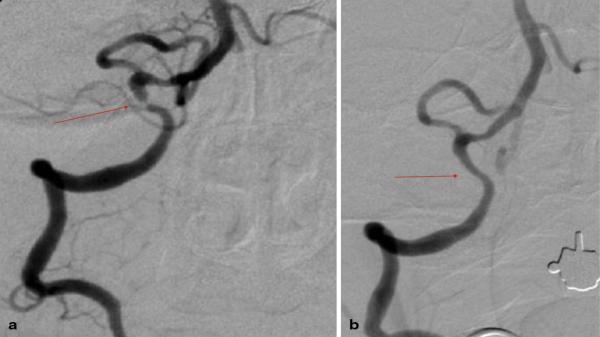

Στενώσεις ενδοκράνιων αγγείων – Ενδείξεις αντιμετώπισης

• Στενώσεις ενδοκράνιων αγγείων – Ενδείξεις αντιμετώπισης